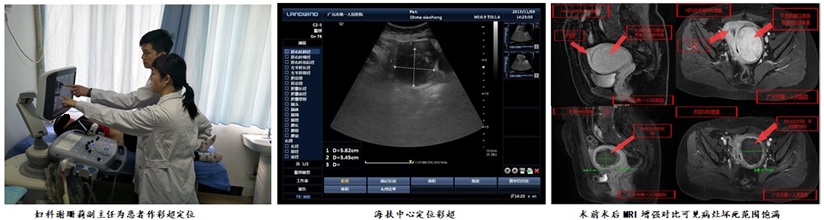

患者王女士,41岁,在3年多前的一次检查中发现自己患有子宫肌瘤,因为担心失去子宫、害怕疼痛和手术后留下难看的瘢痕,迟迟不敢到医院治疗。在偶然的机会得知广元市第一人民医院海扶治疗中心开展的“无创手术”既可以“切除”肌瘤,又可以保留子宫,还不会留下疤痕。经过反复查阅资料、咨询医生后,王女士于2017年12月26日到我院妇科就诊。 经过精心的术前准备, 12月28日,王女士在我院海扶中心接受了HIFU高强度聚焦超声治疗,病灶大小6+cm,手术过程顺利,病灶完美消融。整个海扶治疗过程历时73分钟(辐照时间900S;平均功率400W;治疗强度:740S/h;总能量36000J),术中患者生命体征平稳,耐受佳,配合度好,病灶内出现明显的团块状灰度变化,范围饱满,术后造影提示病灶完美消融。术后第二天,患者顺利出院,海扶中心李洁明主治医师仔细的向王女士交待出院后的注意事项:“出院以后要及时复诊,如果出现血糖低、拉肚子、皮肤眼睛发黄等情况,要及时来院诊治……”“有什么情况,随时给我们打电话沟通,保持联系。” 谢珊莉副主任告诉记者:“子宫肌瘤具有多发和易复发的特点,用海扶超声消融治疗子宫肌瘤,是通过超声波发射到体内病灶产生的瞬间高温将病灶灭活、坏死,从而达到控制病灶生长的目的。这是一种保留子宫、可反复多次进行的无创治疗方法,如果其他部位再长出新的肌瘤,可再次进行超声消融治疗。” 为了提升患者生命质量,降低妇科常规手术创伤,我院引进了国际先进的海扶刀治疗系统;该技术的成功开展,依托于医院强大的专业技术人才队伍,在子宫肌瘤、子宫腺肌症、剖宫产瘢痕妊娠、腹壁切口内膜异位症、胎盘植入等妇科良性疾病的无创治疗方面迈出了重要的一步,填补了广元及川陕甘毗邻地区海扶刀无创治疗领域的空白,也为患者的早日康复带来了福音。